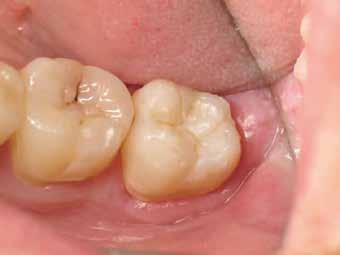

2. ábra: A páciens egy nem megfelelő I. osztályú ezüstamalgám töméssel és II. osztályú szuvasodással jelentkezett. A fog izolálása kofferdám alkalmazásával történt.

3. ábra: A preparálás, a bondozás és a kompozit felvitele után. (Megjegyzés: némi kompozit túlfolyás látható a mesiális doboz axiális falain).

4. ábra: A durva finírozás után a restauráció pereme sima és anatómiailag is megfelelő.